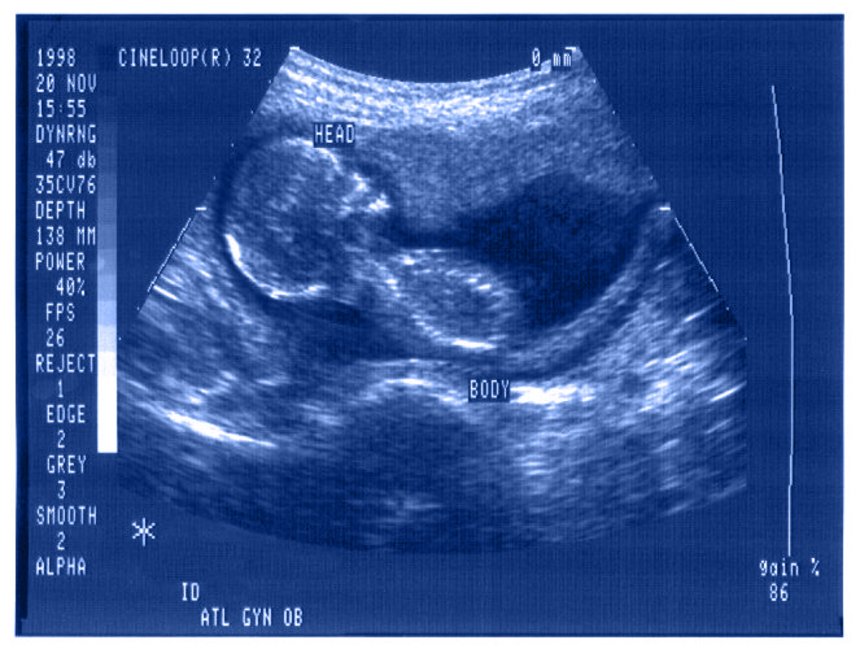

"Płód jako osoba, płód jako pacjent - kulturowe i bioetyczne wymiary i konsekwencje zjawiska upodmiatawiania płodu " - wykład w MS2